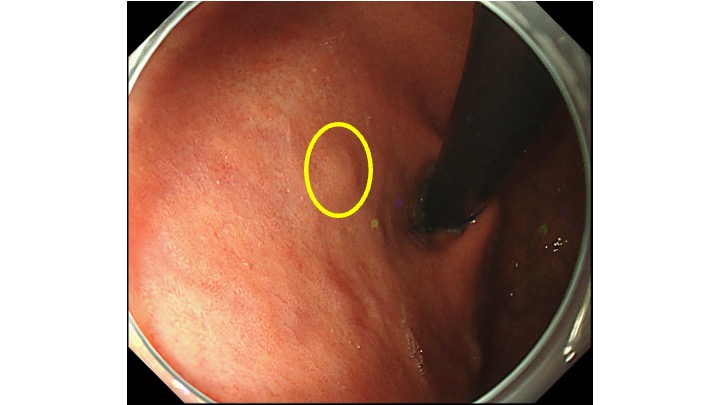

拡大観察すると、領域(境界明瞭)のある癌がわかるかと思います。

通常観察にもどると、黄色の枠に病変があります。